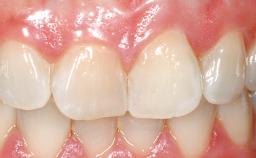

A 33-year-old female patient presented with an upper left central incisor that required extraction after a failed endodontic therapy. The tooth had been traumatized when the patient was a teenager and had undergone several endodontic treatments, including two apicectomy procedures. The patient was in good health and did not smoke. Clinical examination showed that the patient had a high lip line. In full smile, the gingival margins of the upper teeth were visible to the first molars. The gingival margins of central incisors 11 and 21 were only just showing. Examination of tooth 21 confirmed that the tooth was mobile and had hypererupted by 1 mm.

Lip Line No exposure of papillae Exposure of papillae Full exposure of mucosa margin

Periodontal Phenotype Low-scalloped, thick Medium-scalloped, medium-thick High-scalloped, thin